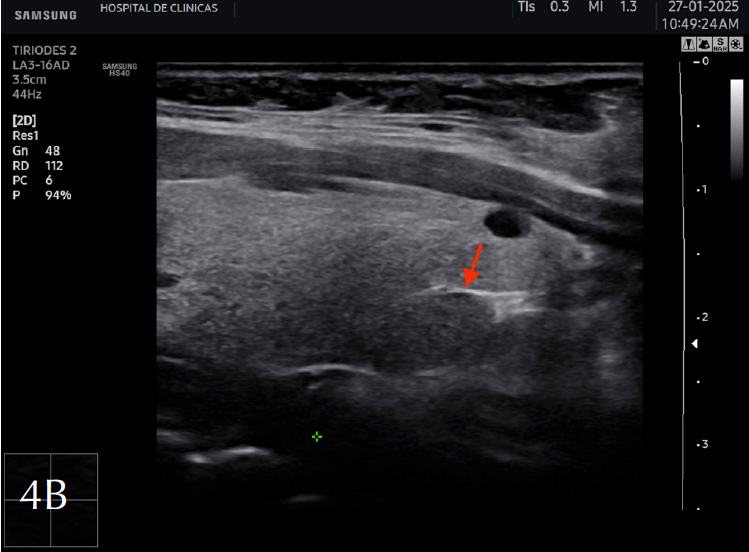

La eco estructura es homogénea, los márgenes son regulares y presenta una cápsula ecogénica, su vascularización es escasa. El rango de referencia para una tiroides normal es de entre cinco y diez vasos visibles dentro de la exploración de cada lóbulo valorado con Doppler color2. Se ha descripto que hasta un 50% de los individuos presentan lóbulo piramidal (Figura 3a y 3b). Este sector, en general, es similar en ecogenicidad, homogeneidad y vascularización al istmo y los lóbulos. En la superficie posterior de los lóbulos tiroideos, especialmente en el segmento inferior, puede visualizarse el tubérculo de Zuckerkandl, un ejemplo de este se puede observar en la figura 4a y 4b. Este es un tabique hiperecogénico fibroso que a menudo genera sombra posterior. Se forma por la extensión del tejido tiroideo de las áreas laterales de los lóbulos hacia el sector posterior, y a menudo exhibe una disminución de la ecogenicidad detrás del mismo. Este proceso puede imitar una lesión tiroidea o paratiroidea y causar dificultades en la interpretación2.